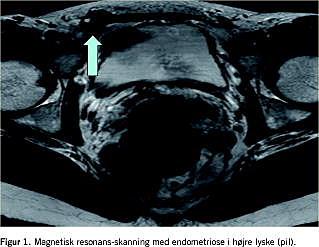

III. En 30-årig kvinde var henvist af en praktiserende gynækolog til Gynækologisk Afdeling med mangeårig anamnese med smertefuld hævelse i højre lyske. Cyklisk smertevariation med maksimum intramenstruelt. Der fandtes en palpatorisk ansamling i højre lyske, som ved UL udmåltes til 1 × 1,5 cm. Supplerende magnetisk resonans (MR)-skanning viste 14 × 19 × 24 mm stort område suspekt for endometriose i den laterale del af højre rectusmuskel 1 cm under hudniveau (Figur 1 ). Kvinden blev behandlet med p-piller med god effekt.